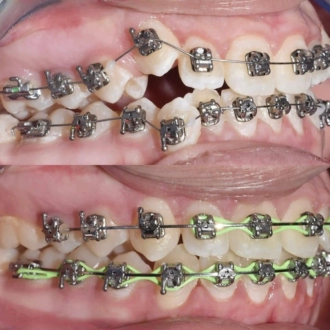

Результат коррекции металлической брекет-системой

Результат коррекции самолигирующей брекет-системой

Результат коррекции элайнерами

Результат коррекции керамической брекет-системой